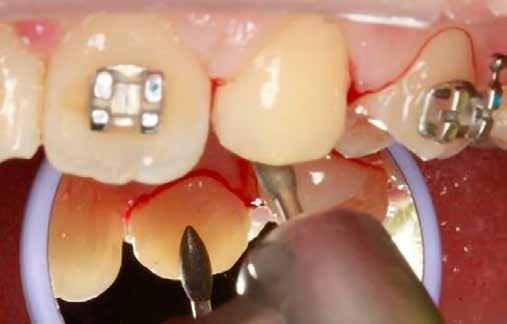

sok korrigálása, valamint az impaktálódott fog előtöréséhez szükséges hely megteremtését követően, egy merev acél ív segítségével stabilizáltuk a fogakat. Ezt követően elvégeztük a jobb felső nagymetszőfog sebészi feltárását. A fog koronáját csupán lágyrész borította, ezért nem volt szükség a csontállomány elvételére. A felszabadítás során egy 975

nm-es hullámhosszon pulzáló üzemmódban alkalmazott lézert használtunk (LaserHF standard, Hager & Werken). A teljesítménye 3 W, az aktív ciklus-idő 50%-os, a vezetőszál átmérője pedig 0,4 mm volt (2. ábra). A lézert 150 másodpercen keresztül alkalmaztuk. A fogat borító lágyrészek eltávolítását követően egy láncos brekettet rögzítettünk a metszőfog bukkális felszínére. A műtétet követően nem tapasztaltunk vérzést, nem alakult ki oedema, valamint a páciens sem számolt be fájdalom vagy bármely egyéb kellemetlenség fennállásáról. A felszabadítást követően a páciens minden hónapban háromszor jelent meg a felszabadított területre ránövő lágyrészek és az íny lézeres eltávolítása céljából. A beavatkozások során ugyanazt a lézer készüléket használtuk, mint amivel a felszabadítást végeztük. Közvetlenül a felszabadítást követően megkezdtük a fog finom extrudálását a láncos breketthez kötött füzérgumi segítségével.

2. ábra: Az impaktált fog lézerrel asszisztált sebészi feltárása. 3. ábra: A kezelés megkezdését követő 15. hónapban megfigyelhető a sikeres felszabadítást, fogmozgatást és pozicionálást követően látható állapot.